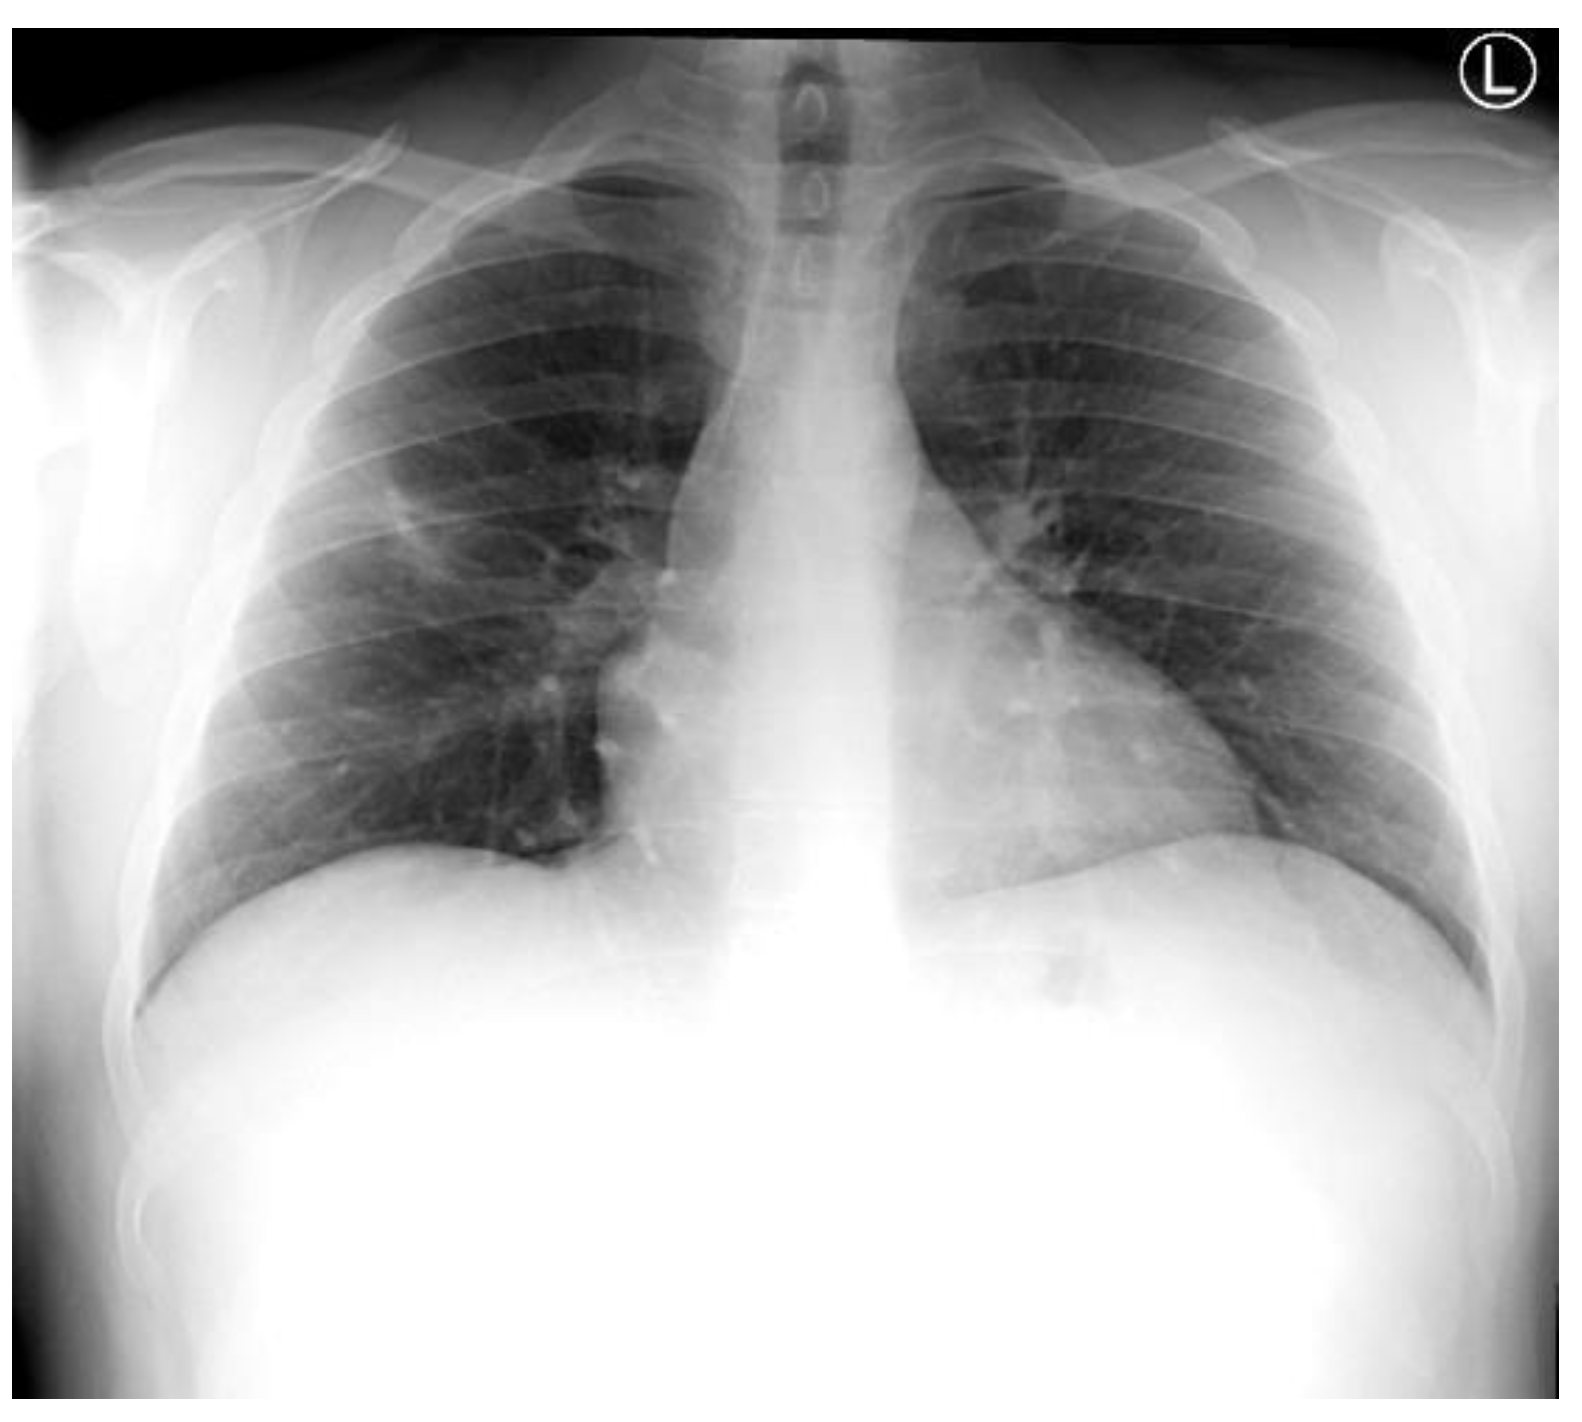

Noting that the patient had been discharged on amoxicillin/clavulanate, an antibiotic to which the isolated H. alvei was noted to be resistant, the patient was recalled for a follow-up review, repeat chest X-ray, and repeat blood tests 11 days after discharge. Remarkably, the repeat chest X-ray revealed significant interval improvement in the cavitating consolidation compared to the index X-ray performed 19 days previously (Figure 3), and repeat blood tests showed resolution of his previously raised inflammatory markers with a leukocyte count of 5.5 × 109/L, and CRP of 3 mg/dL. The patient also reported being symptom free. Following the reassuring review, he was discharged, with a further follow-up chest X-ray organized in six to eight weeks’ time, in accordance with international guidelines. This was performed ten weeks later, and reported almost complete resolution of the previously cavitating lesion in the RUL with only a very small residual lucency. A further follow-up X-ray will be performed in 6-8 weeks to ensure complete resolution.

Figure 3.

Follow-up chest X-ray on day 19 showing significant interval improvement in cavitating consolidation.